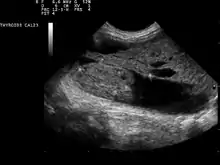

| Ultrasound artifacts showing a "comet tail" from a colloid nodule indicate a benign nodule | |

Ultrasound imaging is useful as the first-line, non-invasive investigation in determining the size, texture, position, and vascularity of a nodule, accessing lymph nodes metastasis in the neck, and for guiding fine needle aspiration cytology (FNAC) or biopsy. Ultrasonographic findings will also guide the indication to biopsy and the long term follow-up.[10] High frequency transducer (7–12 MHz) is used to scan the thyroid nodule, while taking cross-sectional and longitudinal sections during scan. Suspicious findings in a nodule are hypoechoic, ill-defined margins, absence of peripheral halo or irregular margin, fine, punctate microcalcifications, presence of solid nodule, high levels of irregular blood flow within the nodule[11] or "taller-than-wide sign" (anterior-posterior diameter is greater than transverse diameter of a nodule). Features of benign lesion are: hyperechoic, having coarse, dysmorphic or curvilinear calcifications, comet tail artifact (reflection of a highly calcified object), absence of blood flow in the nodule, and presence of cystic (fluid-filled) nodule. However, the presence of solitary or multiple nodules is not a good predictor of malignancy. Malignancy is only diagnosed when ultrasound findings and FNAC report are suggestive of malignancy.[11] The TI-RADS (Thyroid Imaging Reporting and Data Systems) are sonographic classification systems which describe the suspicious findings of thyroid nodules.[12] It was first proposed by Horvath et al.,[13] based on the BI-RADS (Breast Imaging Reporting and Data System) concept. Several systems were subsequently proposed and adopted by international scientific societies. Their main aims are to characterize the risk of malignancy of nodules to better select nodules to submit to fine-needle aspiration cytology.[14] Another imaging modality, which is ultrasound elastography, is also useful in diagnosing thyroid malignancy especially for follicular thyroid cancer. However, it is limited by the presence of adequate amount of normal tissue around the lesion, calcified shell around a nodule, cystic nodules, coalescent nodules.[15]